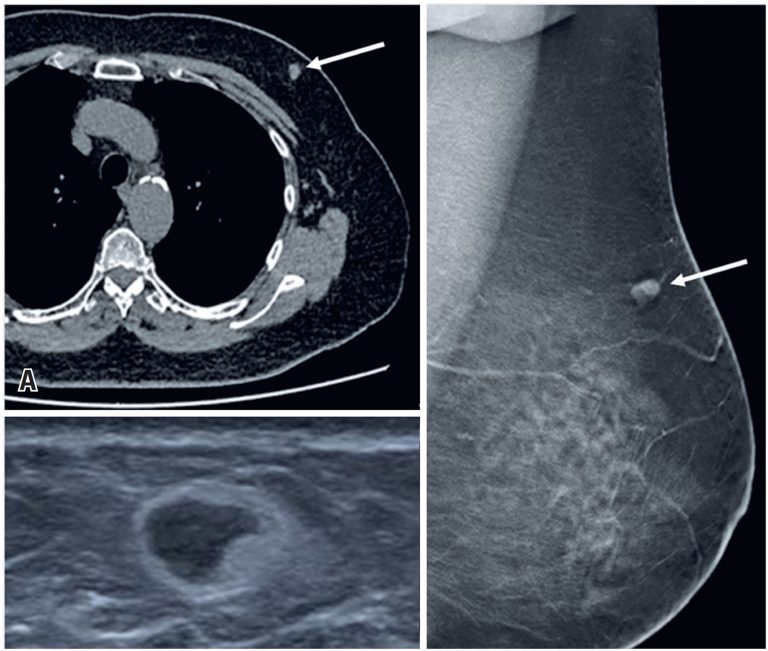

Incidentally detected breast lesions: a pictorial essay of malignant and benign findings

DOI: 10.31744/einstein_journal/2025RW0681

ABSTRACT Incidentalomas are lesions incidentally identified in patients undergoing imaging for unrelated reasons. Breast incidentalomas have a high correlation with malignancy, occurring in over 40% of cases. Consequently, their interpretation poses significant challenges for radiologists who must discern the findings that may present a potential risk to the patient. This pictorial review presents different incidental breast lesions revealed through cross-sectional imaging. We further review key concepts related to such incidentalomas.

Keywords: Breast neoplasms; Diagnostic imaging; Incidental findings; Incidentalomas; Positron emission tomography computed tomography; Tomography, x-ray computed